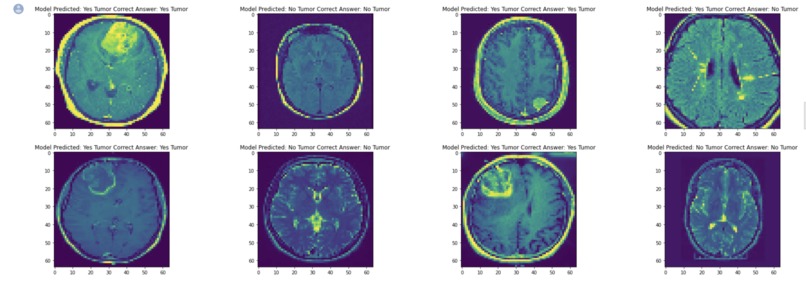

We designed an AI algorithm to actually take patient ultrasounds or any scan in general and use machine learning to train the module to detect some of the more common issues we see in hospitals. Specifically, use a piece of technology known as Convolutional Neural Networks.

The model was able to accurately determine if there was a tumour!